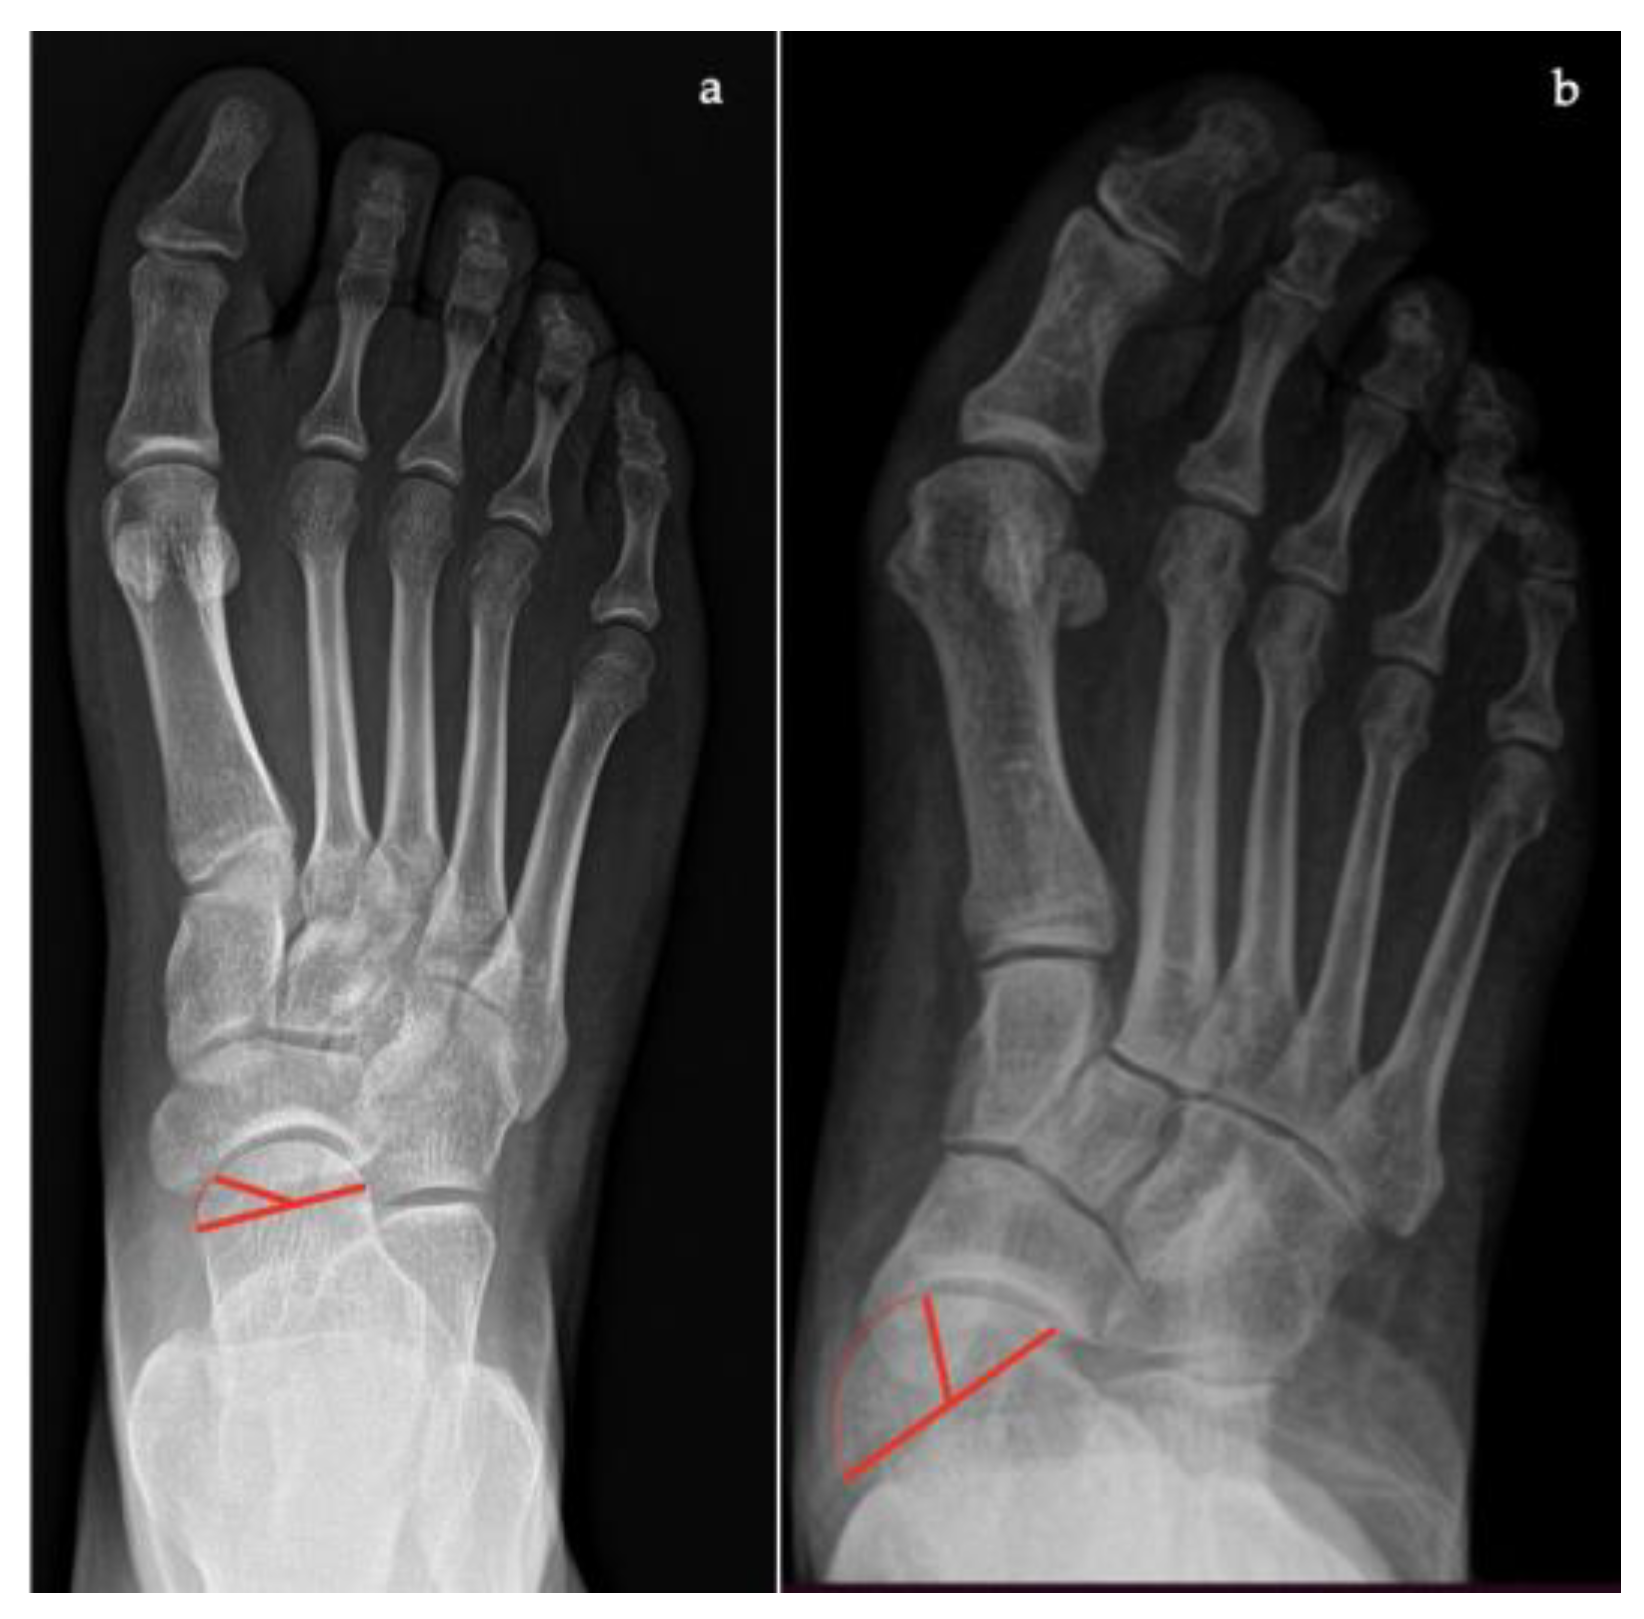

- Talonavicular coverage angle, between the line that joins the medial and lateral articular margins of the talus, and the line that joins the medial and lateral articular margins of the navicular, it represents forefoot abduction (normal, <7°; flatfoot, >7°) (Figure 2);

- Talonavicular uncoverage percentage, the percentage of the talus that is not in contact with the navicular medially, useful to evaluate forefoot abduction (normal, 10% to 30%; flatfoot >30%) (Figure 3);

- Talar incongruency angle (normal, 5° = –26°; flatfoot >26°), is formed by the intersection between a line from the most lateral point of the articular surfaces of the talus and the navicular, and a line from the lateral aspect of the talar neck (in its most narrow segment) to the lateral point of the talar articular surface (Figure 4).